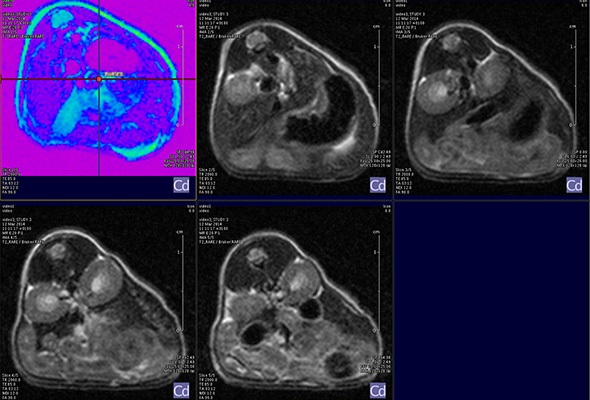

I think that also the low-field, let’s say the low/intermediate field to work at the 1 Tesla for instance as in the case of this beautiful Icon system, this gave us unique possibilities. Anytime we use a gadolinium-based agent or more in general a paramagnetic basic agent the best field is the 1 Tesla.

So, we can show that there is a real advantage of working at 1 Tesla in comparison to for instance 7 or 9 Tesla when one is using a relaxation enhancer to target a specific epitope in the region of interest.